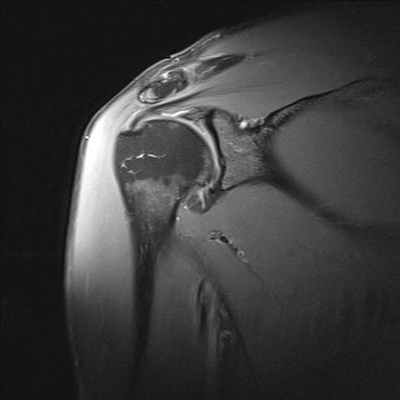

МРТ признаки повреждения акромиально-ключичного сочленения на уровне плечевого сустава

МРТ плечевого сустава